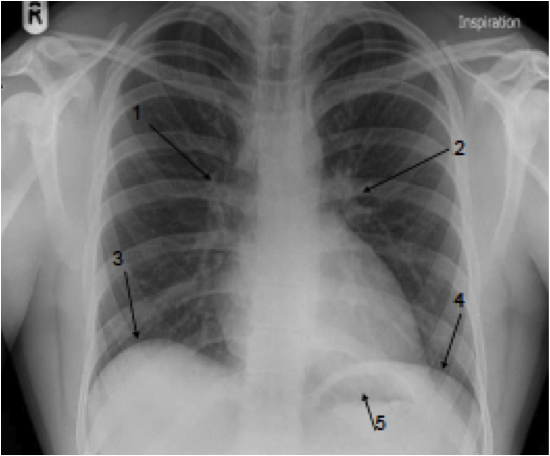

What can you see on this X-ray?

1) Right Hilum

2) Left Hilum

3) Right hemidiaphragm

4) Left hemidiphargm

5) Gastric bubble